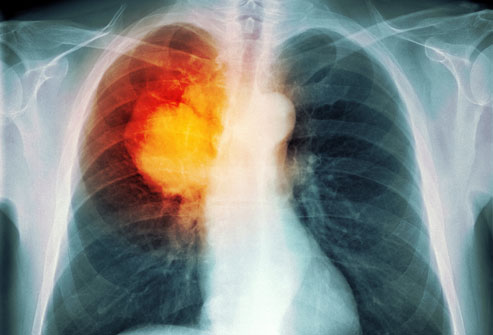

He was twelve when he smoked his first cigarette. It was one of the happiest and most important moments of his life. It made him throw up. His second cigarette, and most of the ones that followed, had the opposite effect. They quieted the nausea that coursed through his restless blood. They calmed his storms.